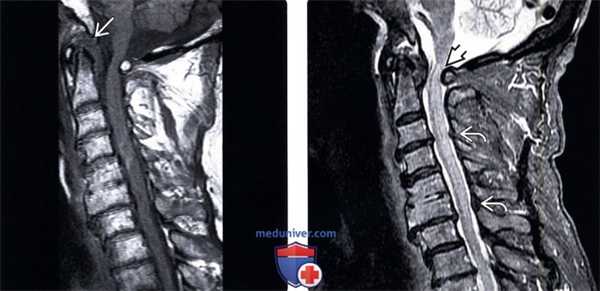

(Слева) Т1-ВИ, сагиттальная проекция: низкоинтенсивная псевдо-опухоль, расположенная позади зубовидного отростка и вызывающая сдавление вентрального листка твердой мозговой оболочки и спинного мозга. Также здесь отмечается и задняя компрессия спинного мозга за счет смещенной кпереди задней дуги атланта.

(Справа) На STIR МР-И видны признаки пирофосфатной артропатии атлантоаксиального сочленения с формированием псевдо -паннуса, сдавливающего спинной мозг, и миеломаляции на фоне переднего подвывиха С1. Обратите внимание на признаки кальцификации желтой связки, ставшей в данной случае дополнительной находкой.

(Слева) Т2-ВИ: пример состояния, требующего дифференциального диагноза с пирофосфатной артропатией. В данном случае это ревматоидный артрит, сопровождающийся «проседанием» черепа на фоне проксимальной транслокации зубовидного отростка в большое затылочное отверстие вследствие несостоятельности связочного аппарата.

(Справа) Т2-ВИ: случай спондилита С1-С2, также включенного в дифференциально-диагностический ряд. Определяются признаки флегмоны С1-С2 сочленения, характеризующейся гиперинтенсивностью сигнала, что кардинально отличает ее от пирофосфатной артропатии, изменения при которой характеризуются низкой интенсивностью сигнала.